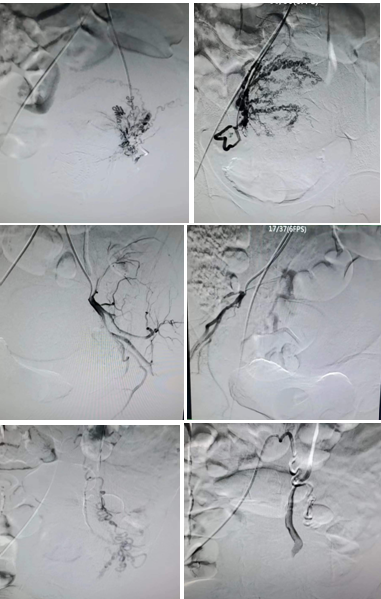

患者38岁,既往3次剖宫产史,2次人流史。本次妊娠16周+5天,B超提示胎盘下缘后方与子宫前壁下段分界欠清,可疑胎盘植入。产科医师评估引产风险极大,有发生子宫破裂、难治性产后出血、子宫切除甚至危及生命的可能。陈思攀医生立即组织产科、心内科和介入手术室,组成MDT团队,讨论决定进行引产前子宫动脉栓塞术,以最大程度减少引产术中出血等。由于患者妊娠次数较多,子宫动脉错综复杂,经过两个小时的介入手术,患者多支子宫供血动脉栓塞满意。次日顺利施行钳刮引产术,出血量仅为260ml(预估未栓塞情况下,出血量至少800ml以上),现患者已顺利康复出院。